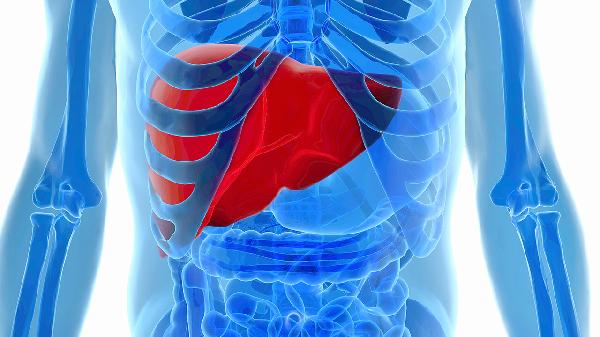

深夜刷手機看到這條消息時,手指突然停在半空——47歲,正當年富力強的年紀,脂肪肝竟成了無聲的劊子手。很多人以為肝區偶爾隱痛只是熬夜的代價,直到體檢單上出現”脂肪肝”三個字才慌了神。其實肝臟就像24小時運作的化學工廠,當脂肪原料堆積超標,流水線遲早要癱瘓。